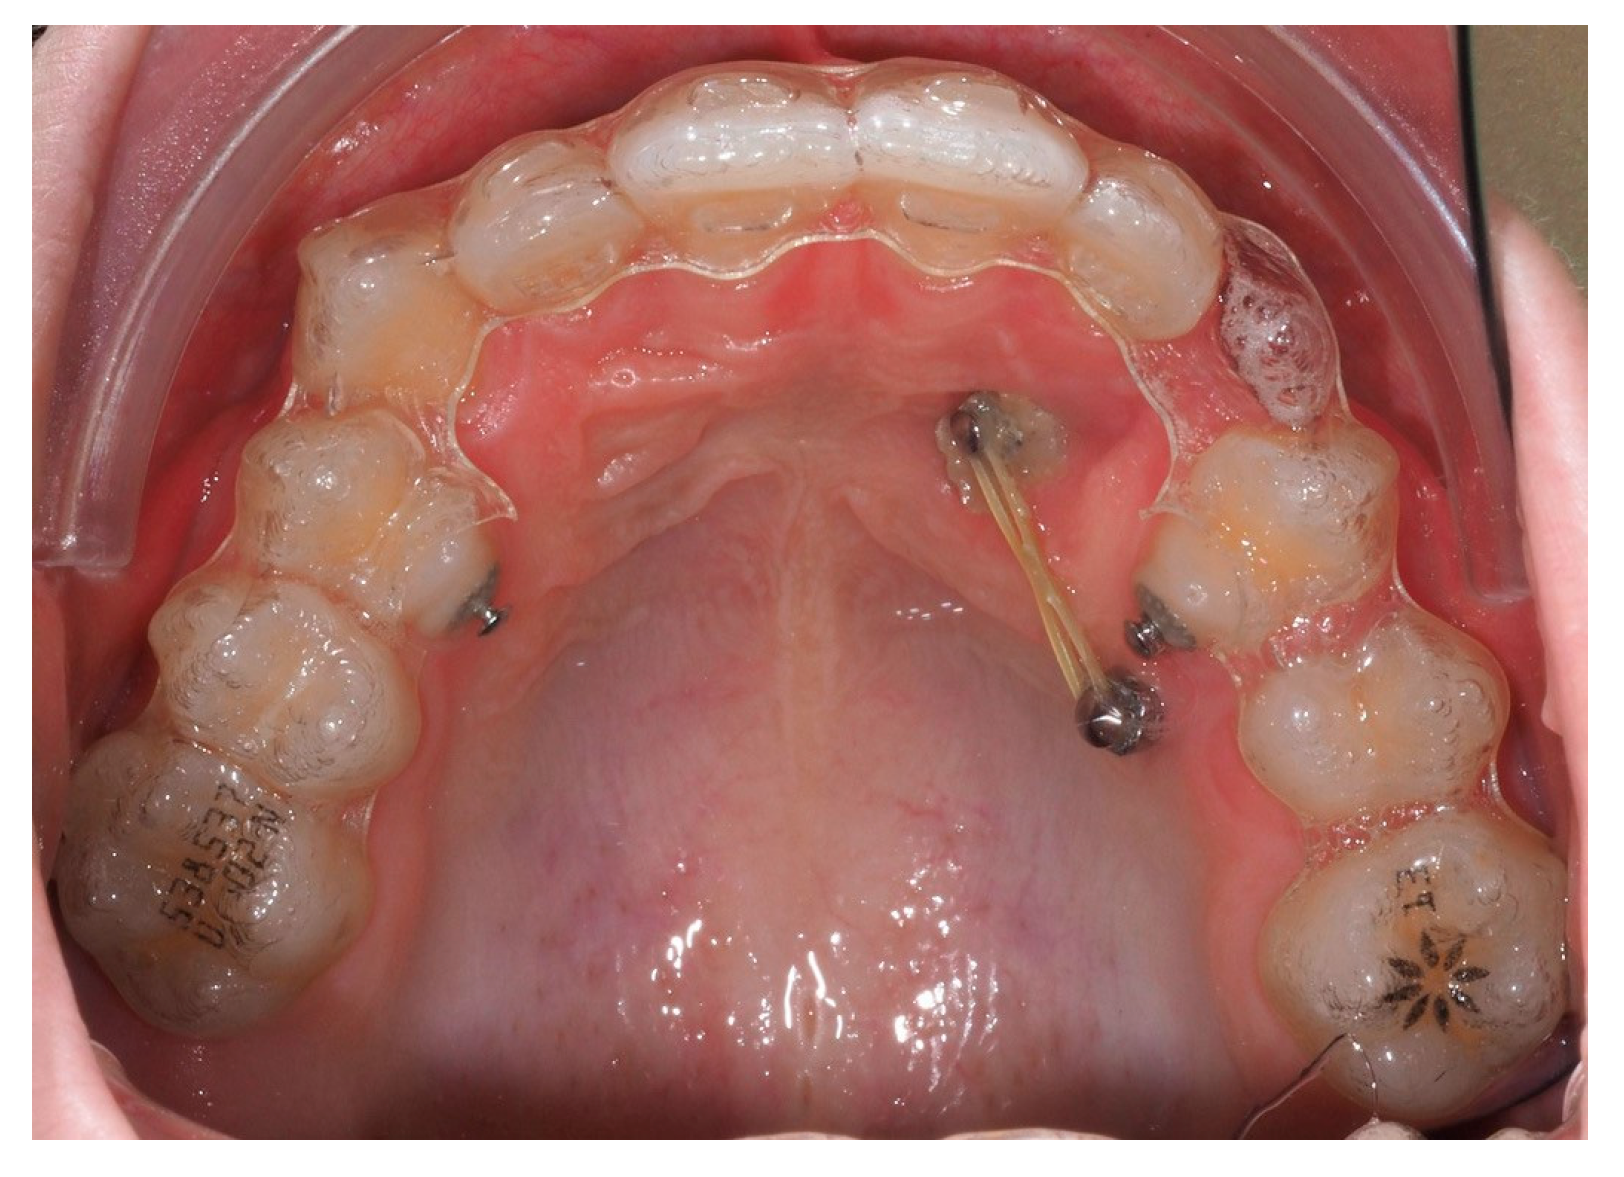

As traction progressed, the sectional appliance was extended to tooth 21 (Figure 19). A palatal button was bonded on tooth 23 to facilitate cross elastic application for vestibular movement (Figure 20). At 20 months, the bracket on tooth 23 was progressively repositioned more cervically and mesially to aid extrusion and derotation (Figure 21). A button was bonded on tooth 22 to support a wire for additional vertical anchorage. Cross elastics were also used between the palatal side of tooth 23 and buttons on teeth 33 and 34, while another elastic connected tooth 22 to 33 (Figure 22).

Figure 19.

Extension of the sectional fixed appliance up to tooth 21, with an additional tube placed on this tooth; 18 months of treatment.

Figure 20.

Palatal button on tooth 23 for cross elastic to assist in its vestibularization; 18 months of treatment.